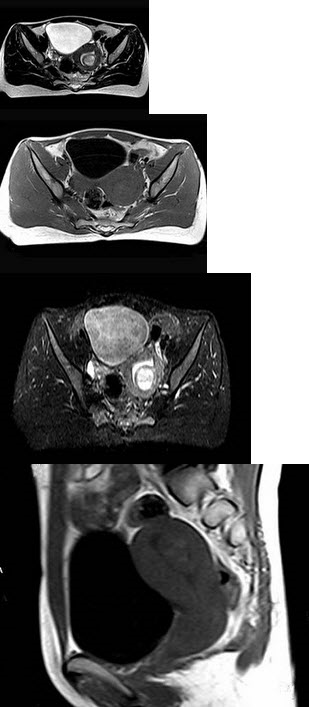

女,30岁,婚后1年未育,有轻度痛经史,腹腔镜检查发现左侧卵巢子宫内膜异位囊肿,直径2cm

女,32岁,婚后3年未孕,有轻度痛经史,腹腔镜检查发现左侧卵巢子宫内膜异位囊肿,直径4cm

A.子宫内膜异位症